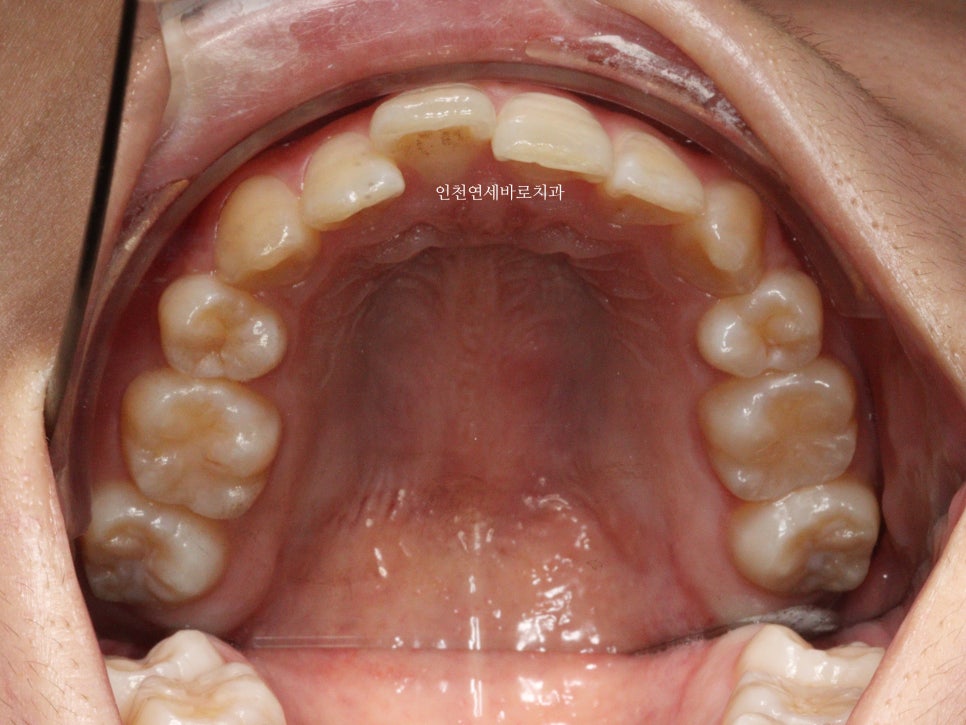

변화모습입니다.

그리고 치료가 마무리 된 후의 모습입니다.

부분교정으로 앞니만 철사를 붙여서도 비슷한 효과를 볼 수 있었을지 모릅니다.

하지만 치아의 삭제가 많은 양 동반되지 않았다면 앞니가 분명 뻗쳐나왔을것입니다.

하지만 인비절라인은 전체교정에 준하는

치아와 주변조직에 무리가 되지 않는 범위에서의 확장을 만들어낼 수 있어

앞니의 뻗침을 최소화 할 수 있는 장점이 있습니다.